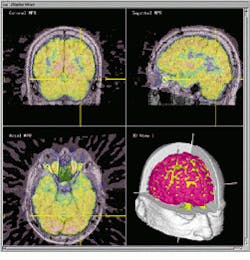

Positron emission tomography yields functional information that can be important in determining areas of low metabolic activity or activity related to a particular brain function (see Fig. 3). Because of this, research teams at the MNI have combined MR and PET data on the Viewing Wand system to better understand the metabolic activity of the brain.

Orthogonal slices of combined MR and PET images are displayed with a 3-D display of object surfaces derived from the original MRI and PET images. PET activity in each slice is indicated by a color scale that is superimposed on the underlying gray-scale MRI. The relative contribution of each data set to the final image is under the interactive control of the operator. The position of the surgical probe in relation to each data set is indicated by a cross-hair cursor on each of the images and by its representation in the 3-D image.

FIGURE 3. Merged MRI and PET data allow the surgeon to combine physical anatomical structures with metabolic activity. Surface rendering of segmented 3-D objects (bottom right) shows the location of the cortex (red) and PET activation level (yellow).